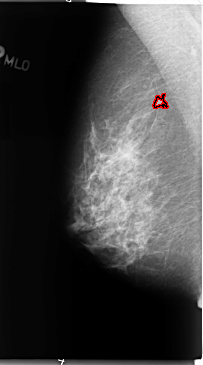

B_3096_1.LEFT_MLO

LEFT_MLO LINES 4712 PIXELS_PER_LINE 2776 BITS_PER_PIXEL 12 RESOLUTION 50 OVERLAY

FILE: B_3096_1.LEFT_MLO.OVERLAY

TOTAL_ABNORMALITIES 1

ABNORMALITY 1

LESION_TYPE MASS SHAPE IRREGULAR MARGINS ILL_DEFINED

ASSESSMENT 3

SUBTLETY 3

PATHOLOGY BENIGN

TOTAL_OUTLINES 1

BOUNDARY